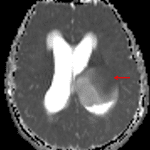

- T1 hypointense, T2 hyperintense, nonenhancing mass measuring 4.6 x 5.5 x 5.8 cm centered in the left thalamus with inferior extension into the left eccentric midbrain, lateral extension into the posterior limb of the left internal capsule, and superior extension into the left frontoparietal periventricular white matter

- Associated obstructive hydrocephalus at the level of the posterior third ventricle and cerebral aqueduct with subependymal edema and supratentorial sulcal effacement

- Dilated optic nerve sheaths and expanded Meckel’s caves relating to elevated intracranial pressure

- Areas of restricted diffusion in the bilateral parahippocampal gyri which could represent ischemic infarcts, sequelae of recent seizure activity, or less likely additional areas of tumor involvement

Diffuse midline glioma